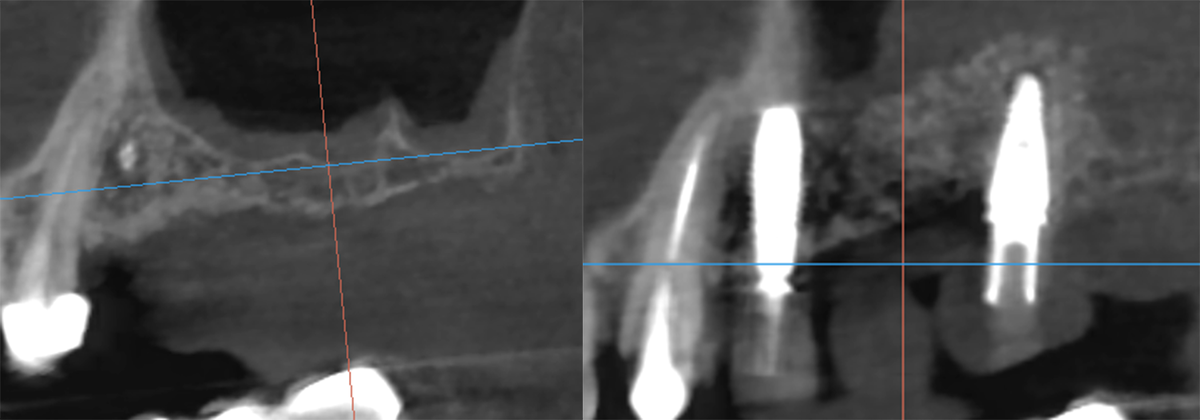

До синус-лифтинга(слева) и после (справа)